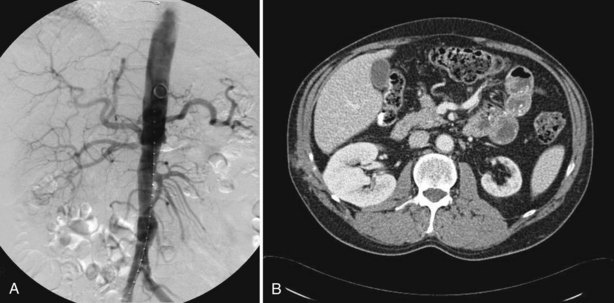

The arteriogram in perimedial fibroplasia may give the appearance of arterial beading, but careful observation shows that the caliber of the normal segment of the vessel is not exceeded by the “bead” (Fig. 39–6). This fact, along with the frequent occurrence of extensive collateral circulation, differentiates this lesion angiographically from that of medial fibroplasia. Perimedial fibroplasia produces severe stenosis, and, although complicating thrombosis or dissection is relatively uncommon, progressive obstruction with ischemic renal atrophy occurs in almost all patients managed nonoperatively.

Figure 39–6 Renal arteriogram in a patient with perimedial fibroplasia shows slightly irregular, yet severe, stenosis of the midrenal artery (arrows) associated with extensive collateral circulation to the kidney. The small size of the arterial irregularities and the presence of collateral circulation distinguishes this lesion radiographically from medial fibroplasia.

(From Novick AC. Renal vascular hypertension in children. In: Kelalis PP, King LR, Belman AB, editors. Clinical pediatric urology. Philadelphia: WB Saunders; 1984.)